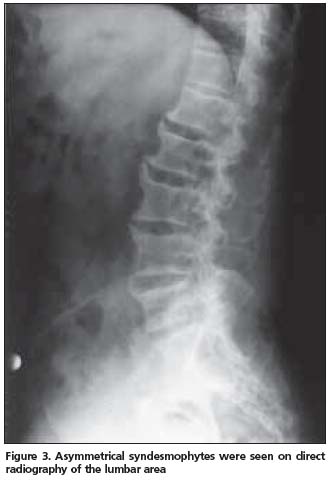

Anterior longitudinal ligament calcification, fusion of multiple facet joints and atypical syndesmophytes were found on cervical spine X-rays (Figure 1) and coarse, asymmetrical syndesmophytes were seen on thoracic (Figure 2) and lumbar spine (Figure 3) X-rays. No abnormalities suggesting PsA or gout were seen on hand and foot radiographs. The magnetic resonance imaging (MRI) of the sacroiliac joint and computerized tomography (CT) of atlanto-axial joint were normal.

PsSpA is observed in 5% of the PsA patients and may be clinically confused with AS[12]. The clinical characteristics of our case also resembled AS. An inflammatory type of low back pain was present and chest expansion was 2 cm. X-rays revealed a predominance of axial involvement. However, a normal sacroiliac joint MRI and lack of a typical syndesmophyte appearance made the AS diagnosis unlikely.